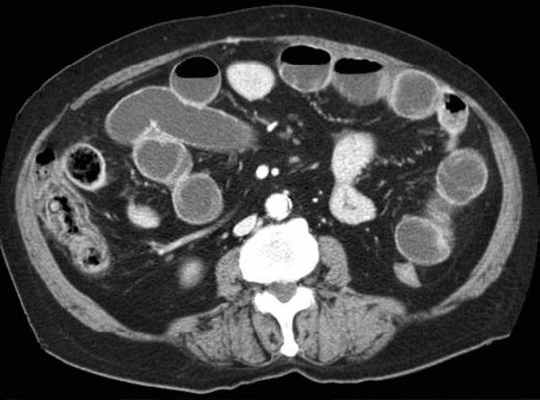

Основным методом окончательной, верифицированой диагностики непроходимости тонкой кишки на данный момент является СКТ/МДКТ с болюсным контрастным услением, являясь золотым стандартом визуализации.

КТ визуализация при простой форме

Хирургическая классификация тонкокишечной непроходимости также является основой классификации, используемой в радиологии. Раличают три формы:

- простая/компенсированная форма

- декомпенсированная форма

- осложнённая форма.

-Расширенные петли тонкой кишки проксимальнее транзиторной зоны (зоны обструкции).

-Под транзиторной зоной надо понимать зонy кишки с очевидной разностью в диаметре просвета между расширенным проксимальным сегментом и местом сужения/обструкции. Визуализация этой зоны зависит от причины и механизма обструкции, а также от проекции расположения петли (аксиально, фронтально и т.д.). К сожалению, обнаружение этой зоны не всегда представляется возможным. При спаечном механизме или воспалении многими хорошо описан признак "птичьего клюва". При обструкции в результате алиментарного болюса транзиторная зона будет выглядеть как гетерогенное образование в просвете кишки без признаков контрастного усиления.

-Спавшиеся петли кишечника дистальнее уровня обструкции.

-Смешанный характер стаза содержимого кишечника в расширенных петлях. Некоторыми авторами описан "фекалоидный" тип стаза, описанный в литературе как "каловое содержимое тонкой кишки", в английской литературе-“small-bowel faeces sign”. Патогенез данного признака включает в себя много факторов:

замедление пассажа содержимого, нарушения механизмов абсорбции и секреции в тонкой кишке, рефлюкс из толстой кишки из-за недостаточности илео-цекального клапана, постановка желудочного зонда. Необходимо помнить, что этот признак неспецифичен при тонкокишечной непроходимости, его также можно определить на УЗИ и обзорной рентгенограмме брюшной полости.

-Нормальные неутолщённые стенки кишечника с гомогенным одинаковым контрастным усилением.

-В тощей кишке рисунок ворсинок слизистой (valvulae conniventes) тонкий, и он одинаково выглядят на всём протяжении.

-Отсутствие патологических изменений толстой кишки, толстая кишка как правило спавшаяся или содержит небольшое количество калового содержимого, распределённого по всему просвету.

-Отсутствие воспалительных изменений в брыжейке и внутрибрюшинном жире.

-Нормальная васкуляризация сосудов брыжейки.

-Отсутствие свободной жидкости в брюшной полости.

Различные КТ сканы при простой форме обструкции, cxематично изображены транзиторные зоны и спайки, которые как "хомут" или "удавка" как-бы душат петлю кишки.